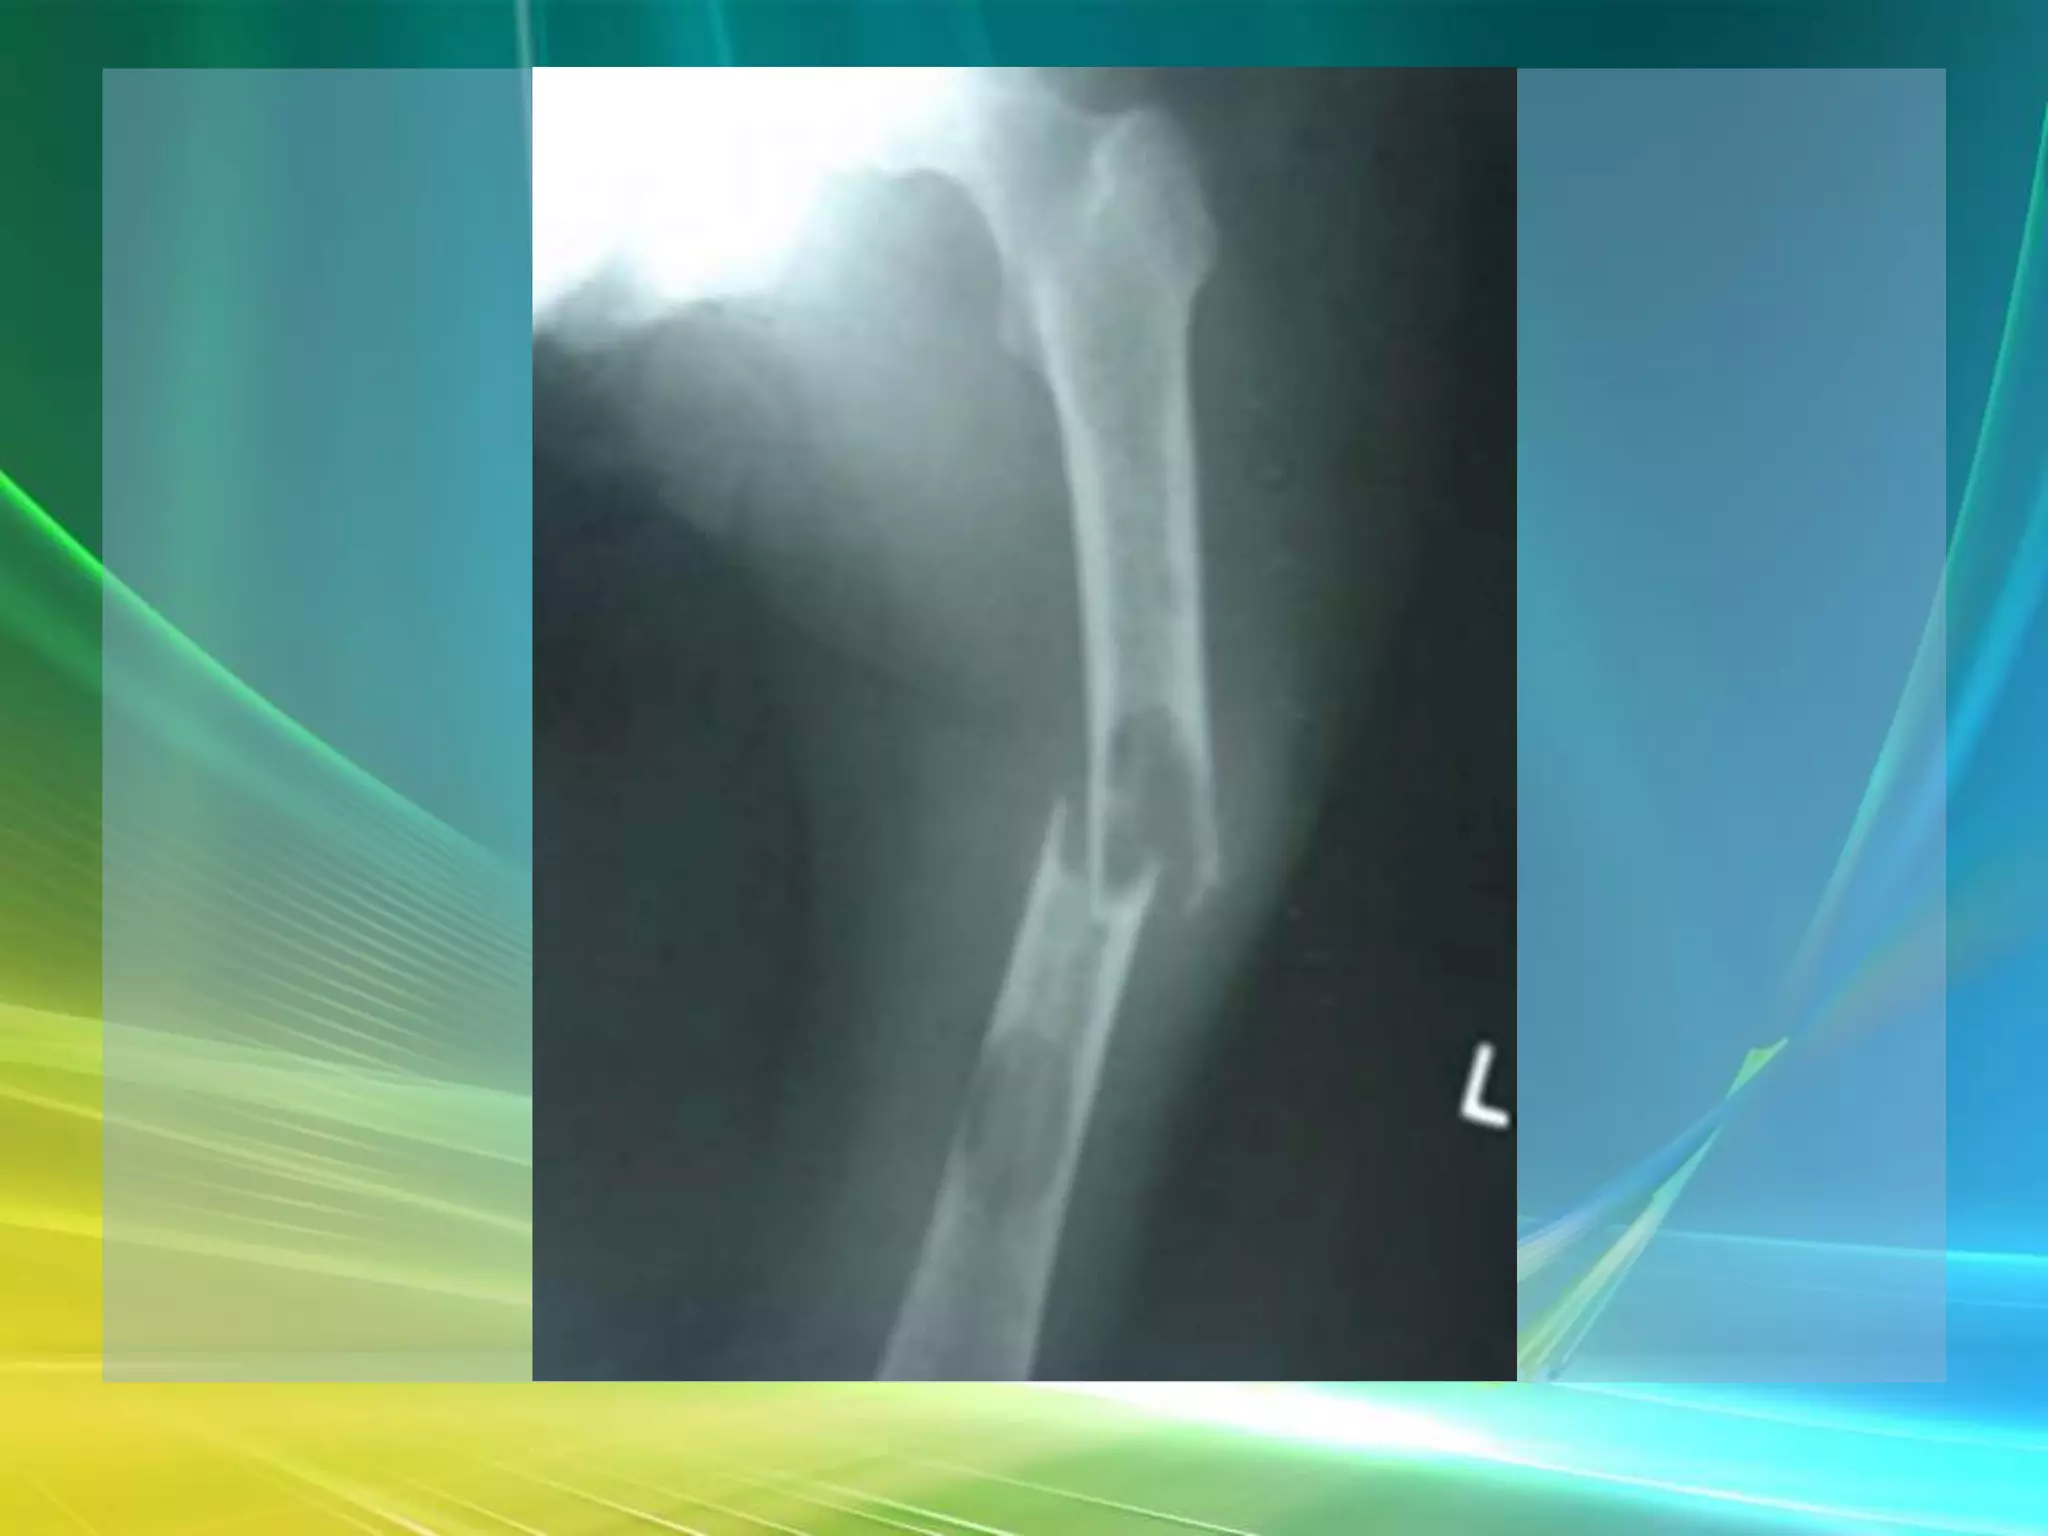

What do you see?